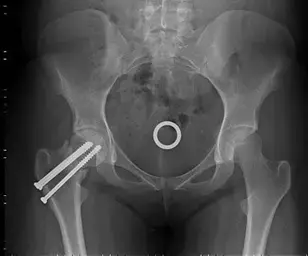

الأشعة السينية قبل وبعد استبدال مفصل الورك.

الأشعة السينية قبل وبعد استبدال مفصل الورك. في هذه الحالة ، تم استخدام المكونات غير الأسمنتية. ## الرعاية بعد الجراحة مباشرة